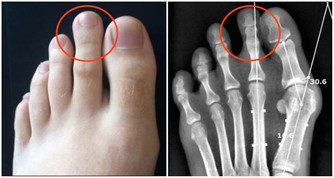

膝蓋關節一直是諸多長輩的困擾 尤其到了中老年又缺乏運動的情況下 很容易伴隨著天氣或者其他原因而不適 可是沒想到這些問題讓一顆便宜隨處可見的洋蔥改善了! 做法: 材料:洋蔥2個,紅葡萄酒500毫升,1瓶普通紅葡萄酒配三個洋蔥。 製法:將洋蔥洗凈,去掉表麵茶色外皮,切成八等份約半月形 將洋蔥洗凈,去掉表將洋蔥裝入玻璃瓶內,加入紅葡萄酒,(將剝下來的外皮也一起加入效果更好 將玻璃瓶蓋好密封,在陰涼地方放置約2至8日。(筆者覺得一星期最好) 將玻璃瓶的洋蔥片,用濾網過濾後,洋蔥、酒分開裝入瓶中,放置在冰箱中冷藏 飲用方法: 一. 每日約一杯(50毫升),年紀大的人每次20毫升左右; 二. 每日飲一至兩次; 三. 浸過酒的洋蔥片一起食用更好; 四. 不喝酒的人,可用兩倍左右的開水稀釋後飲用或每次倒入電鍋內煮約4至5分鐘,蒸發酒精後飲用。 洋蔥治療膝蓋疼效果驚人 看到這裡大家是否覺得很容易呢?究竟又可以治那些病呢? 讓筆者告訴大家,其功效對膝蓋! 疼痛、白內障、老人痴呆的效果相當驚人,日本非常流行。 一. 高血壓的患者,飲了之後血壓正常且安定,也會降低糖尿值,把血糖下降。 二. 每晚都要去幾次廁所的夜晚頻尿症,喝了兩天之後,不可思議的完全恢復正常。 三. 每天夜裡醒來,一直到天亮都不能再入睡的,不食安眠藥不能入睡的不眠症,飲用之後也會全消除。 四. 經常肚子會脹,非常痛苦的便秘症,喝了之後第二天便恢復正常排便。 吃洋蔥的好處 補充:討厭吃洋蔥嗎?看看下面的文章,即使它再不可口,為了身體好,也請多多食用。 【洋蔥比骨質酥鬆症的藥有效】 權威期刊「自然」的最新研究報告指出,洋蔥是最能夠防止骨質流失的一種蔬菜。洋蔥預防骨質流失的效果,甚至比骨質酥鬆症治療藥品還要好。 【洋蔥可以預防膽固醇過高】 據哈佛醫學院心臟科教授克多格爾威治博士指出,每天生吃半個洋蔥,或喝等量的洋蔥汁,平均可增加心臟病人約30%的HDL含量(HDL為高密度脂蛋白膽固醇,一種被認為有助於預防動脈粥狀硬化的膽固醇,也是一種的好的膽固醇。) 【洋蔥可以分解脂肪】 克多博士讓診所里的心臟病人每天吃洋蔥,結果發現洋蔥里所含的化合物也能阻止血小板凝結,並加速血液凝塊溶解。所以,當你享用高脂肪食物時,最好能搭配些許洋蔥,將有助於抵銷高脂肪食物引起的血液凝塊;所以說牛排通常搭配洋蔥一起吃,是很有道理的。 【洋蔥可以對抗哮喘】 洋蔥含有至少三種抗發炎的天然化學物質,可以治療哮喘。由於洋蔥可以抑制組織胺的活動,而組織胺正是一種會引起哮喘過敏症狀的化學物質;據德國的研究,洋蔥可以使哮喘的發作機率降。 【洋蔥可以治療糖尿病】 很久以前,洋蔥就被用來治療糖尿病,到了現代,醫學也證明洋蔥確實能夠降血糖;而且不論生食或熟食,都同樣有效果。原來洋蔥里有一種抗糖尿病的化合物,類似常用的口服降血糖劑甲磺丁胺,具有刺激胰島素合成及釋放的作用。